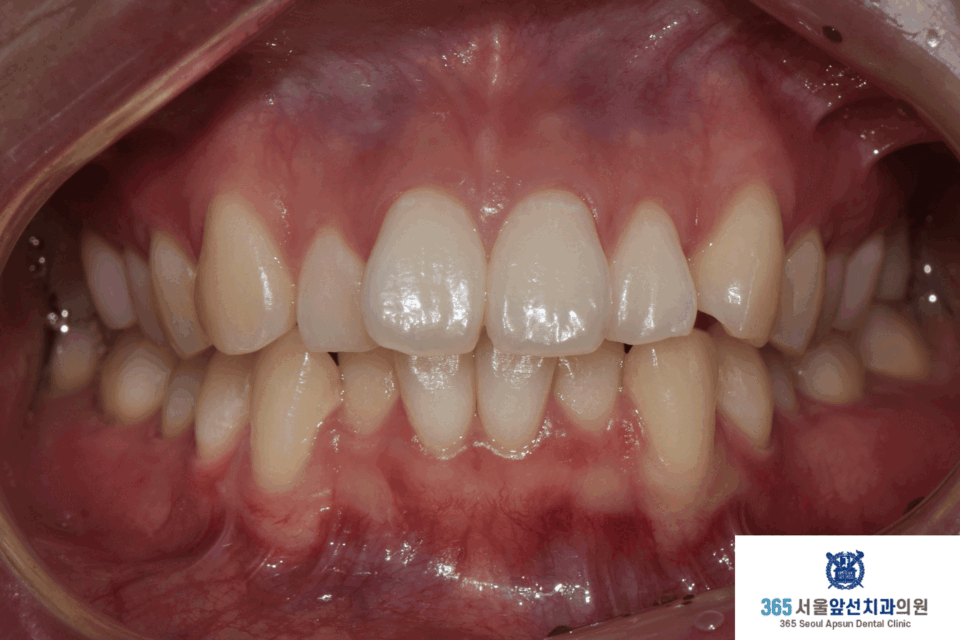

아랫니의 치열이 윗니의 치열보다 후퇴되어있는 2급 부정교합도 있었지만, 환자분은 2급 부정교합은 수정하지 않고 앞니의 치열만 가지런히 하기를 원하셔서 부분 교정으로 진행하였습니다. 이 경우, 2급 부정교합과 수평 피개는 잔존하게 됩니다. 부정교합의 정도에 따라, 치료계획을 좀더 간단하게 수정할 수 있습니다. 전체 교정과 부분 교정의 계획은 꼭 전문의와의 상담을 통해 결정하는 것이 좋습니다. ^^ (그림3) 촬영일자 2025.11.06.